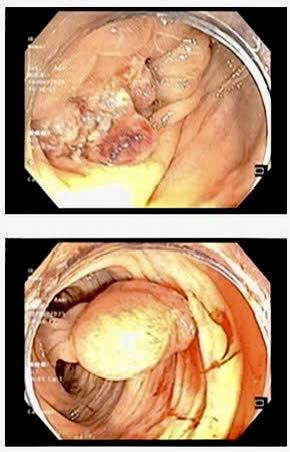

Bệnh nhân nam giới, 26 tuổi (Hải Phòng) đi khám vì đau bụng và mệt mỏi kéo dài. Kết quả nội soi cho thấy một khối u lớn, sùi loét tại đại tràng ngang. Giải phẫu bệnh xác định đây là ung thư biểu mô tuyến đại tràng.

Kết quả nội soi của bệnh nhân 26 tuổi.